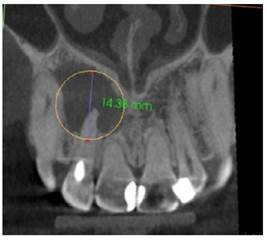

A la Tomografía computarizada de haz cónico (CBCT) se observó una imagen hipodensa que se extendía desde la pieza 1.1, 1.2, 1.3 hasta la pieza 1.4 extendiéndose principalmente hacia el paladar, en el cual se observa perdida de continuidad, las dimensiones de la lesión fueron de 14,38 mm en sentido longitudinal y 15,32 mm en sentido transversal (Figura 2a, b).

Figura 2a Tomografia 03/07/2022; corte coronal. Lesión hipodensa de altura 14,38 mm asociada a la pieza 1.2 en la cual observamos un tratamiento endodóntico inconcluso.